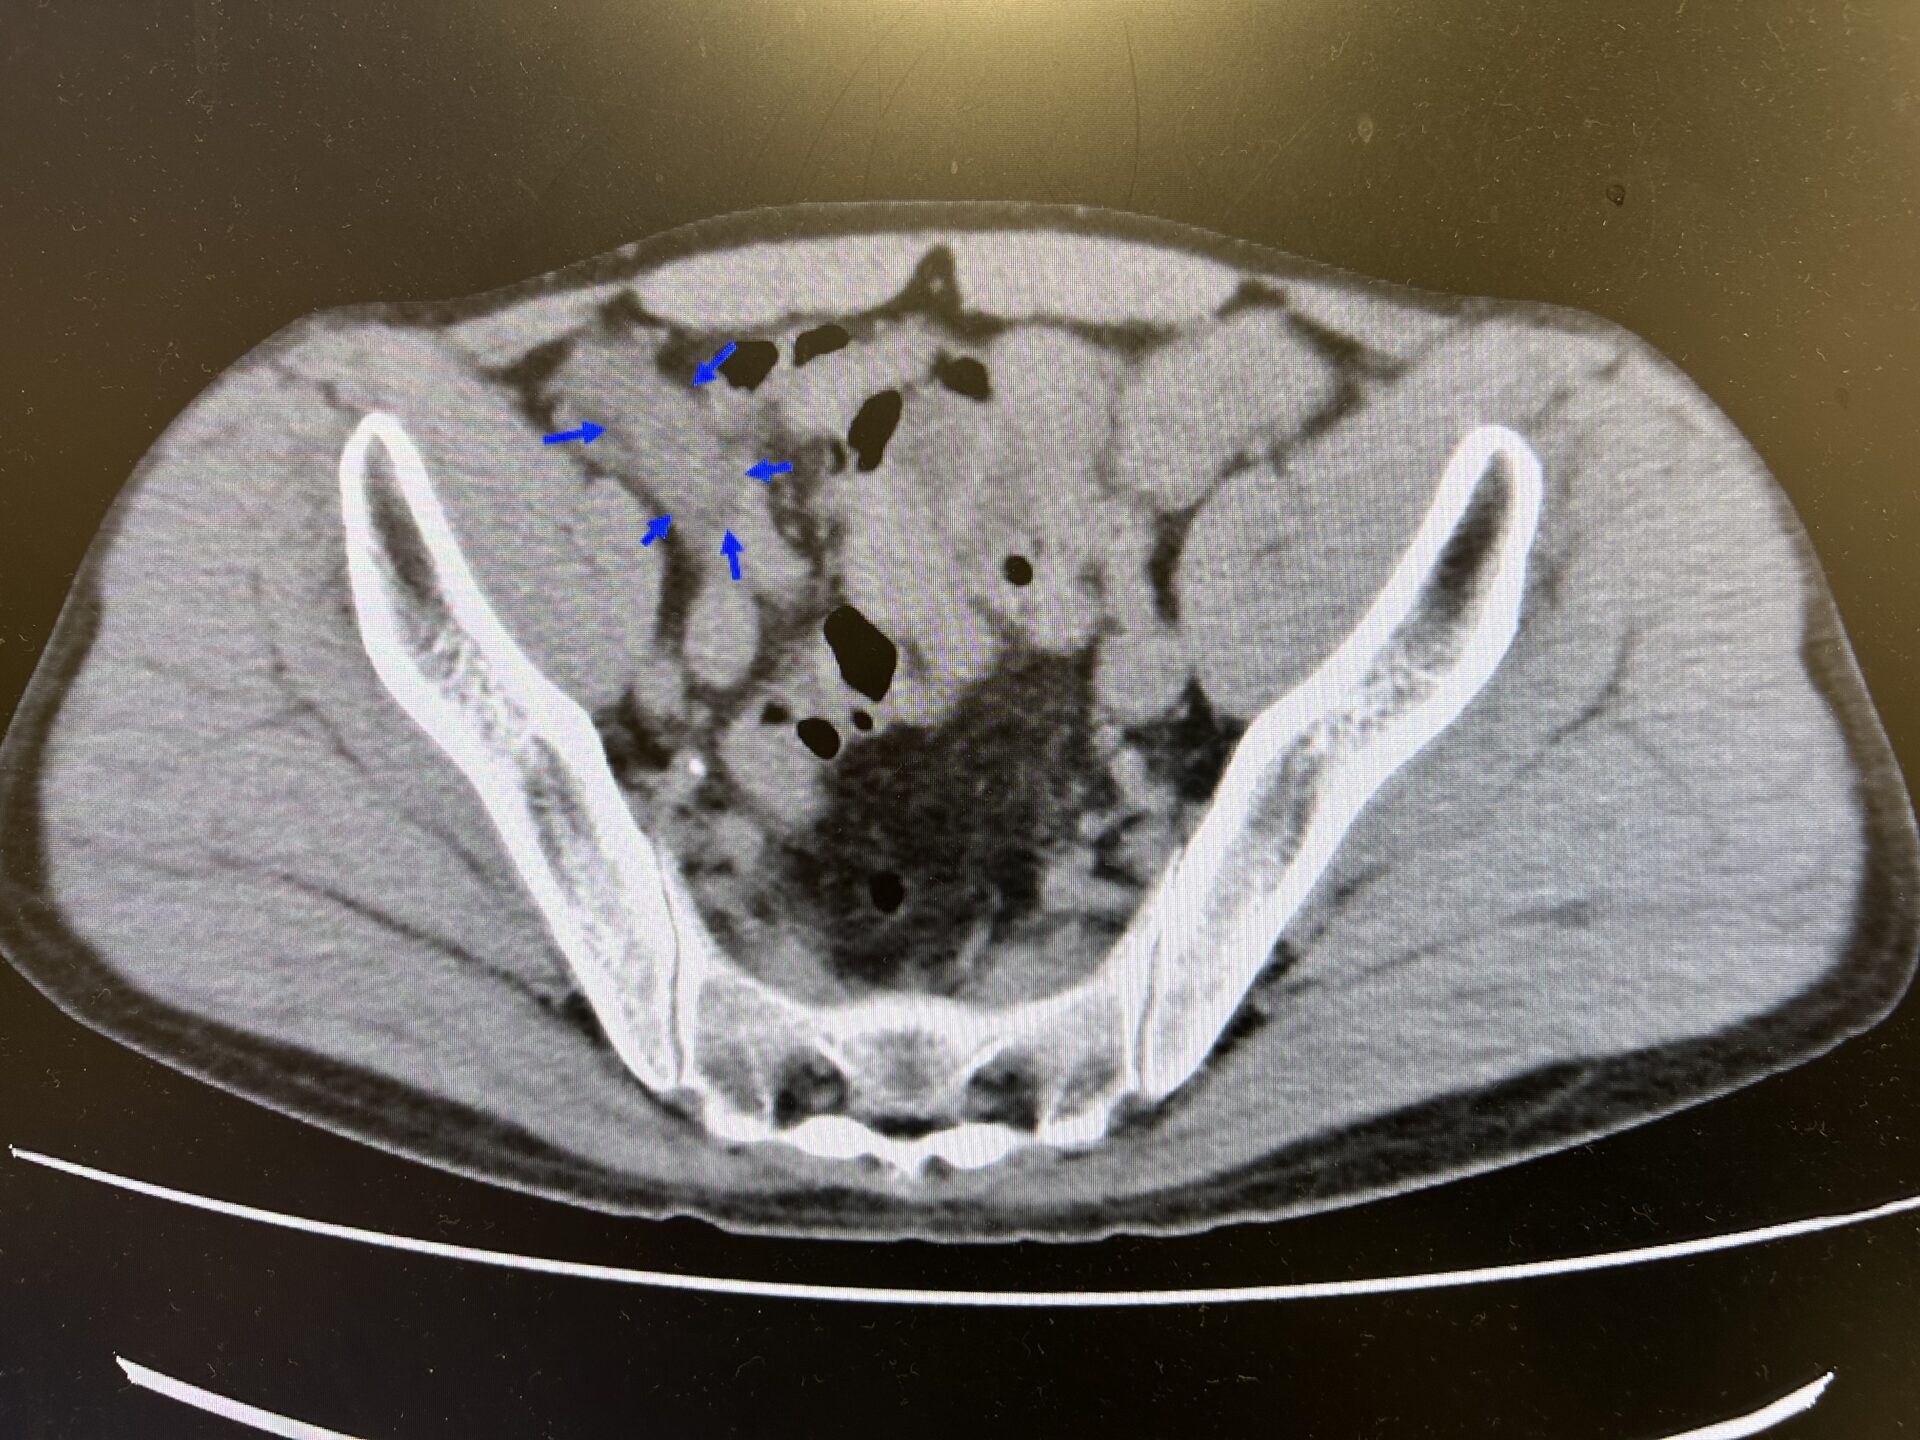

【緊急CT横断像;右下腹部に腫大した虫垂を認めている】

先ほどエコーで認められた虫垂の腫れた部位がやはりCT上でも同様の所見を認め、急性虫垂炎の診断が返ってきました。その後、患者さんには専門家に今後についてしっかりとコンサルトしましょうと説明し、近隣施設の消化器外科に緊急で紹介受診とさせていただきました。